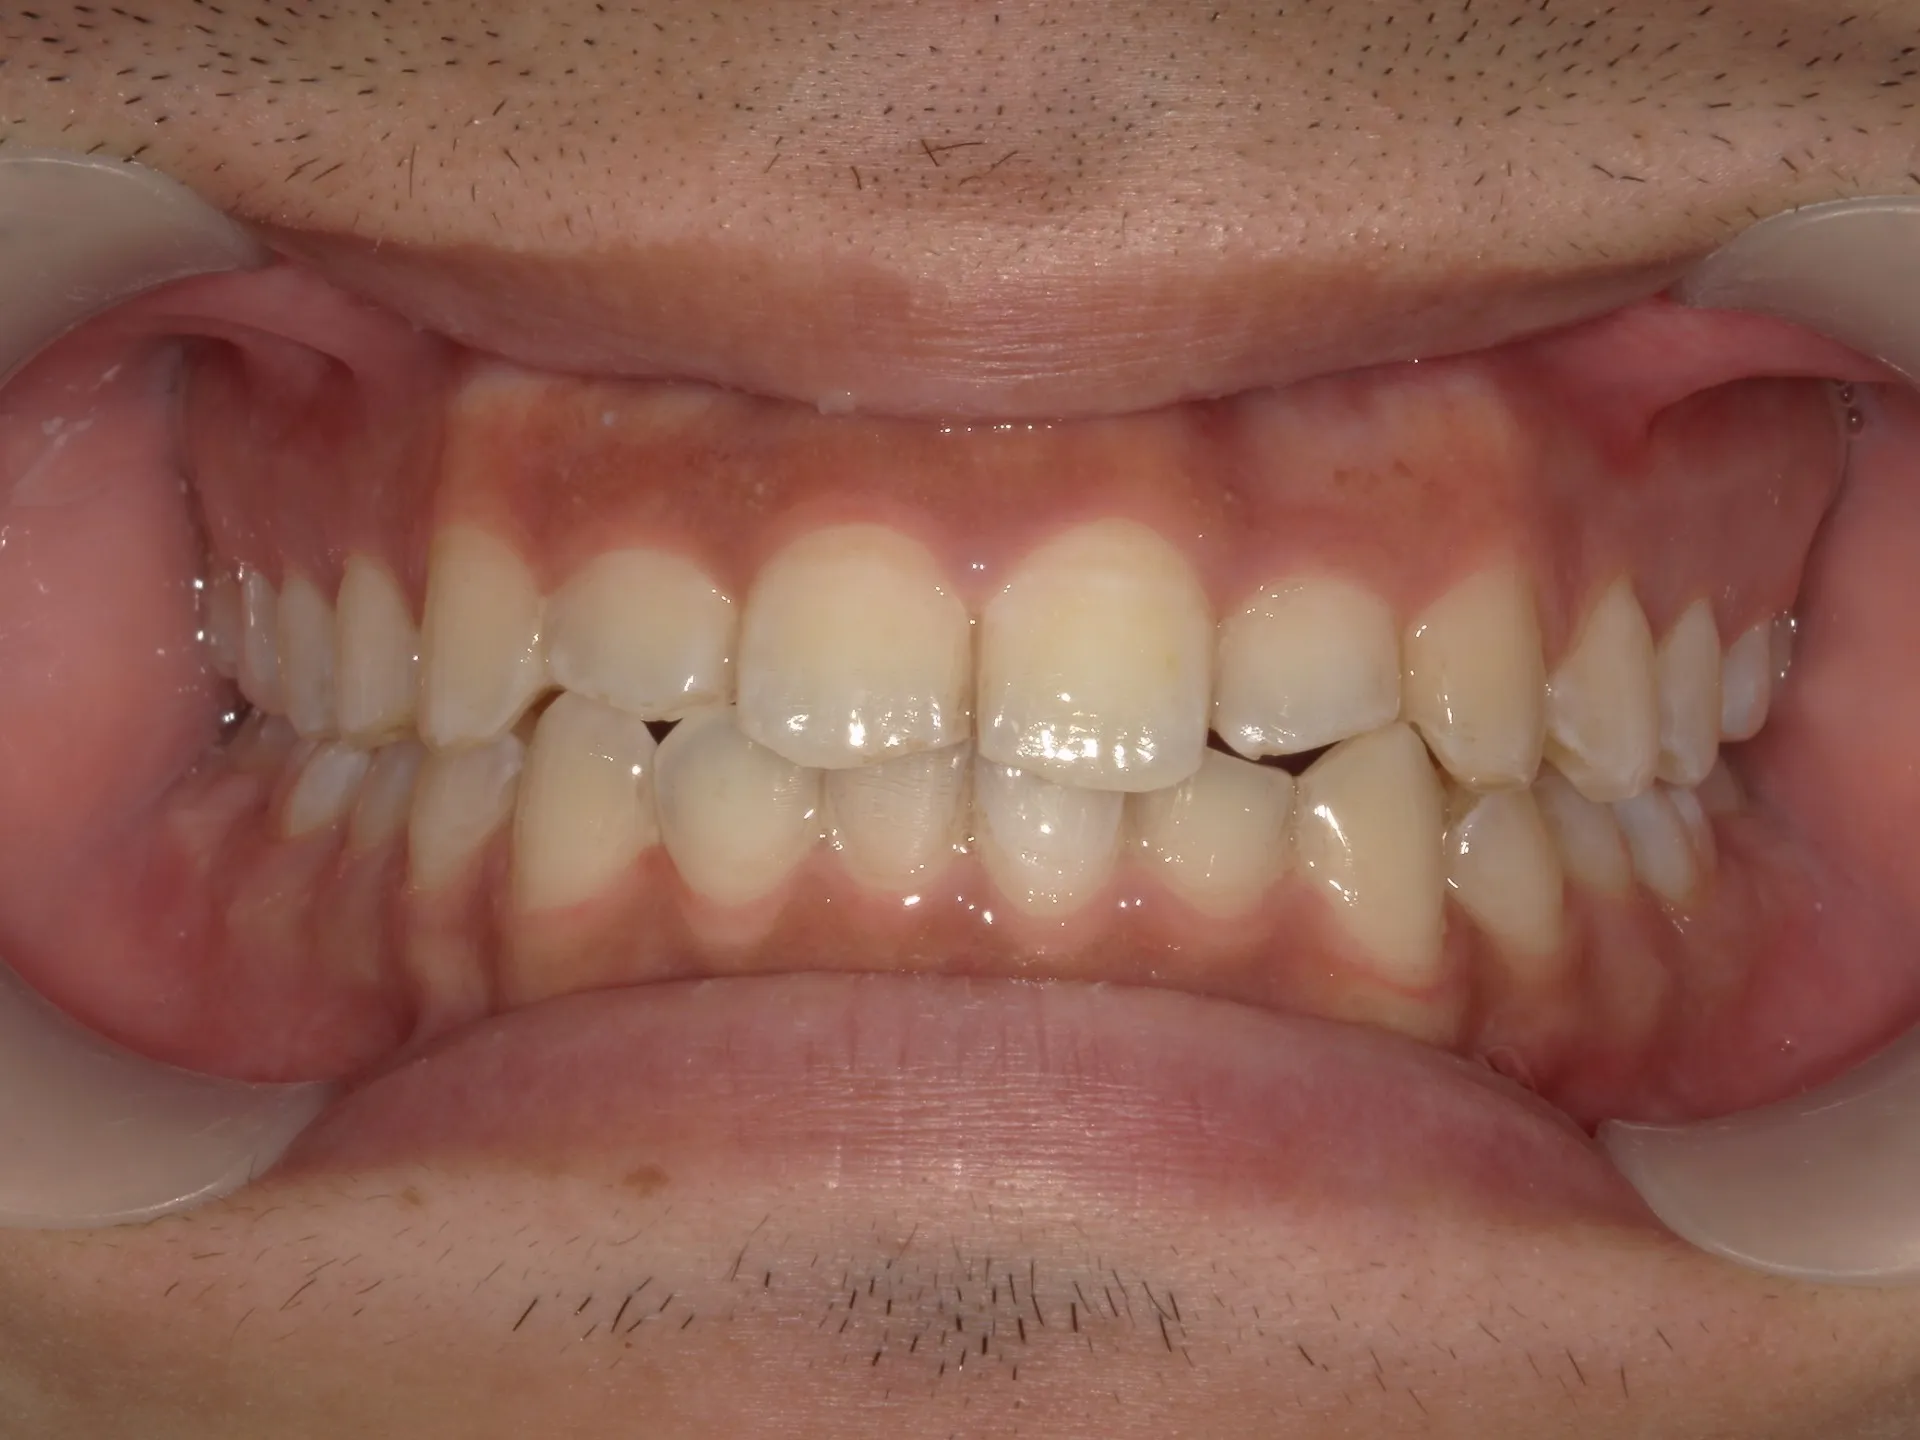

今回は他院さんでインビザライン矯正治療を受けていた患者様を引き継いで当院でインビザライン治療を継続した症例をご紹介致します。

今回はマウスピース矯正を主軸にした矯正ですが、一部ワイヤー矯正も併用して改善しております。